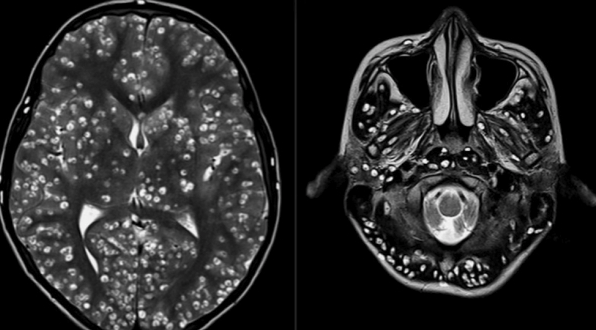

El creciente número de quistes que presentaba dificultó el uso de fármacos antiparasitarios.

Los médicos no lograron revertir la situación debido al creciente número de quistes que presentaba y que dificultó el uso de fármacos antiparasitarios, así que lo trataron con corticoides estándares y medicamentos para evitar ataques epilépticos.

Nada podía evitar que muriera. Padecía ‘neurocisticercosis’, enfermedad parasitaria causada por huevos microscópicos de una tenia porcina que afectan el tejido muscular y que se propagan al cerebro.

El mayor problema de este padecimiento es que sus víctimas pasan mucho tiempo sin presentar síntomas y en este caso, el joven no se sintió mal hasta que la muerte estaba próxima, cuando su corteza cerebral y el tronco encefálico estaban llenos de larvas, informa New England Journal of Medicine.